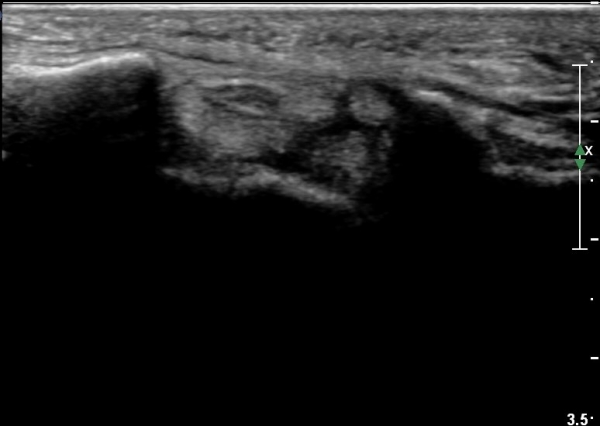

¼ö±Ù°ü ±ÙÀ§ºÎ Ⱦ´Ü¸é°Ë»ç¿¡¼­ Á¤Á߽ŰæÀÇ ºÎÁ¾ µî ƯÀÌ ¼Ò°ßÀÌ º¸ÀÌÁö ¾Ê´Â´Ù(»çÁø 2).